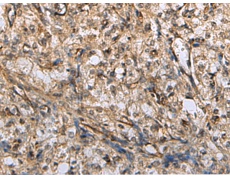

IHC positive control: |

Human brain |

IHC Recommend dilution: |

50-200 |